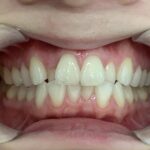

噛み合わせの位置が改善され、歯並びもきれいになりました。

患者様には「すごくきれいになった」と大変ご満足いただきました。